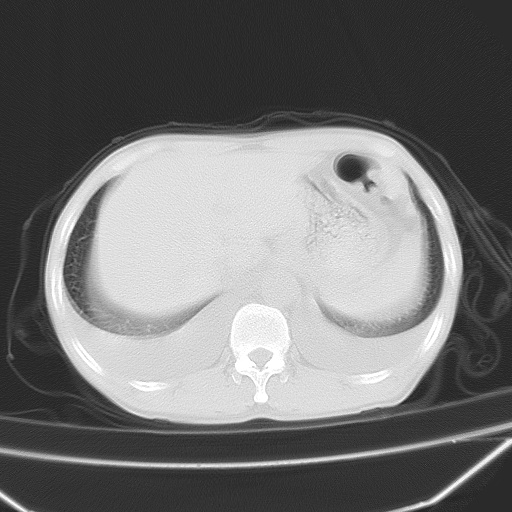

男、42岁、咯血3天。既往有甲亢、贫血、血尿蛋白尿史多年。血象:wbc:6.   中性粒:70.6%。

左心房增大,考虑心衰,肺水肿。

心影增大密度略低,双肺磨玻璃样高密度影及双侧胸腔积液,考虑心功能不全继发双肺肺水肿及双侧胸腔积液。心影密度略低,考虑贫血所致。